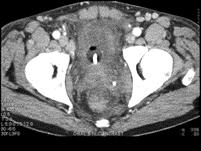

男,45岁,尿频、尿急、尿痛1月余,请根据所示图像,选择最可能诊断 ( )A、膀胱癌B、膀胱炎C、膀胱结石D、膀胱息肉E、膀胱血块

问题 男,45岁,尿频、尿急、尿痛1月余,请根据所示图像,选择最可能诊断 ( )

选项 A、膀胱癌 B、膀胱炎 C、膀胱结石 D、膀胱息肉 E、膀胱血块

答案 B